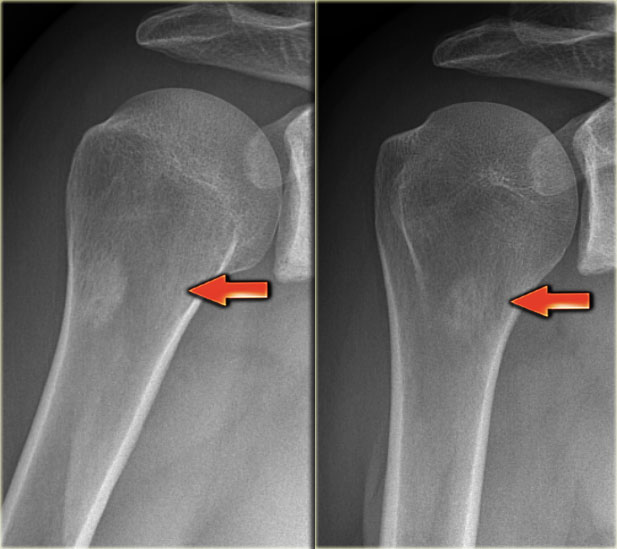

The x-ray demonstrates an eccentric lytic lesion in the proximal femur in a child.

There is surrounding reactive sclerosis.

Histology revealed osteoid osteoma.

Osteoid osteoma may present as a lytic lesion.

X-ray an CT-image of a typical osteoid osteoma in the proximal tibia.

Notice the sclerotic center within the osteolytic lesion (red arrow).

MR-images of the same patient demonstrate cortical thickening and extensive edema.